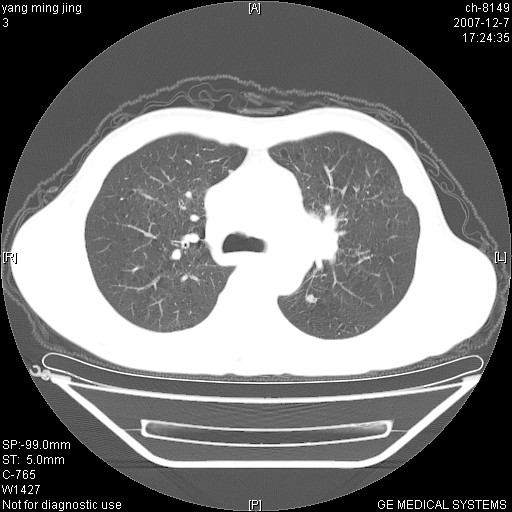

以下是引用zsl6918在2007-12-7 22:22:00的发言:[br]左肺上叶中心性肺癌并肺内及纵隔淋巴结转移,肝内转移。小细胞肺癌可能性大。

以下是引用狙击手在2007-12-8 11:03:00的发言:[br]考虑:左肺上叶中心性肺癌并肺内及纵隔淋巴结转移,肝内转移。